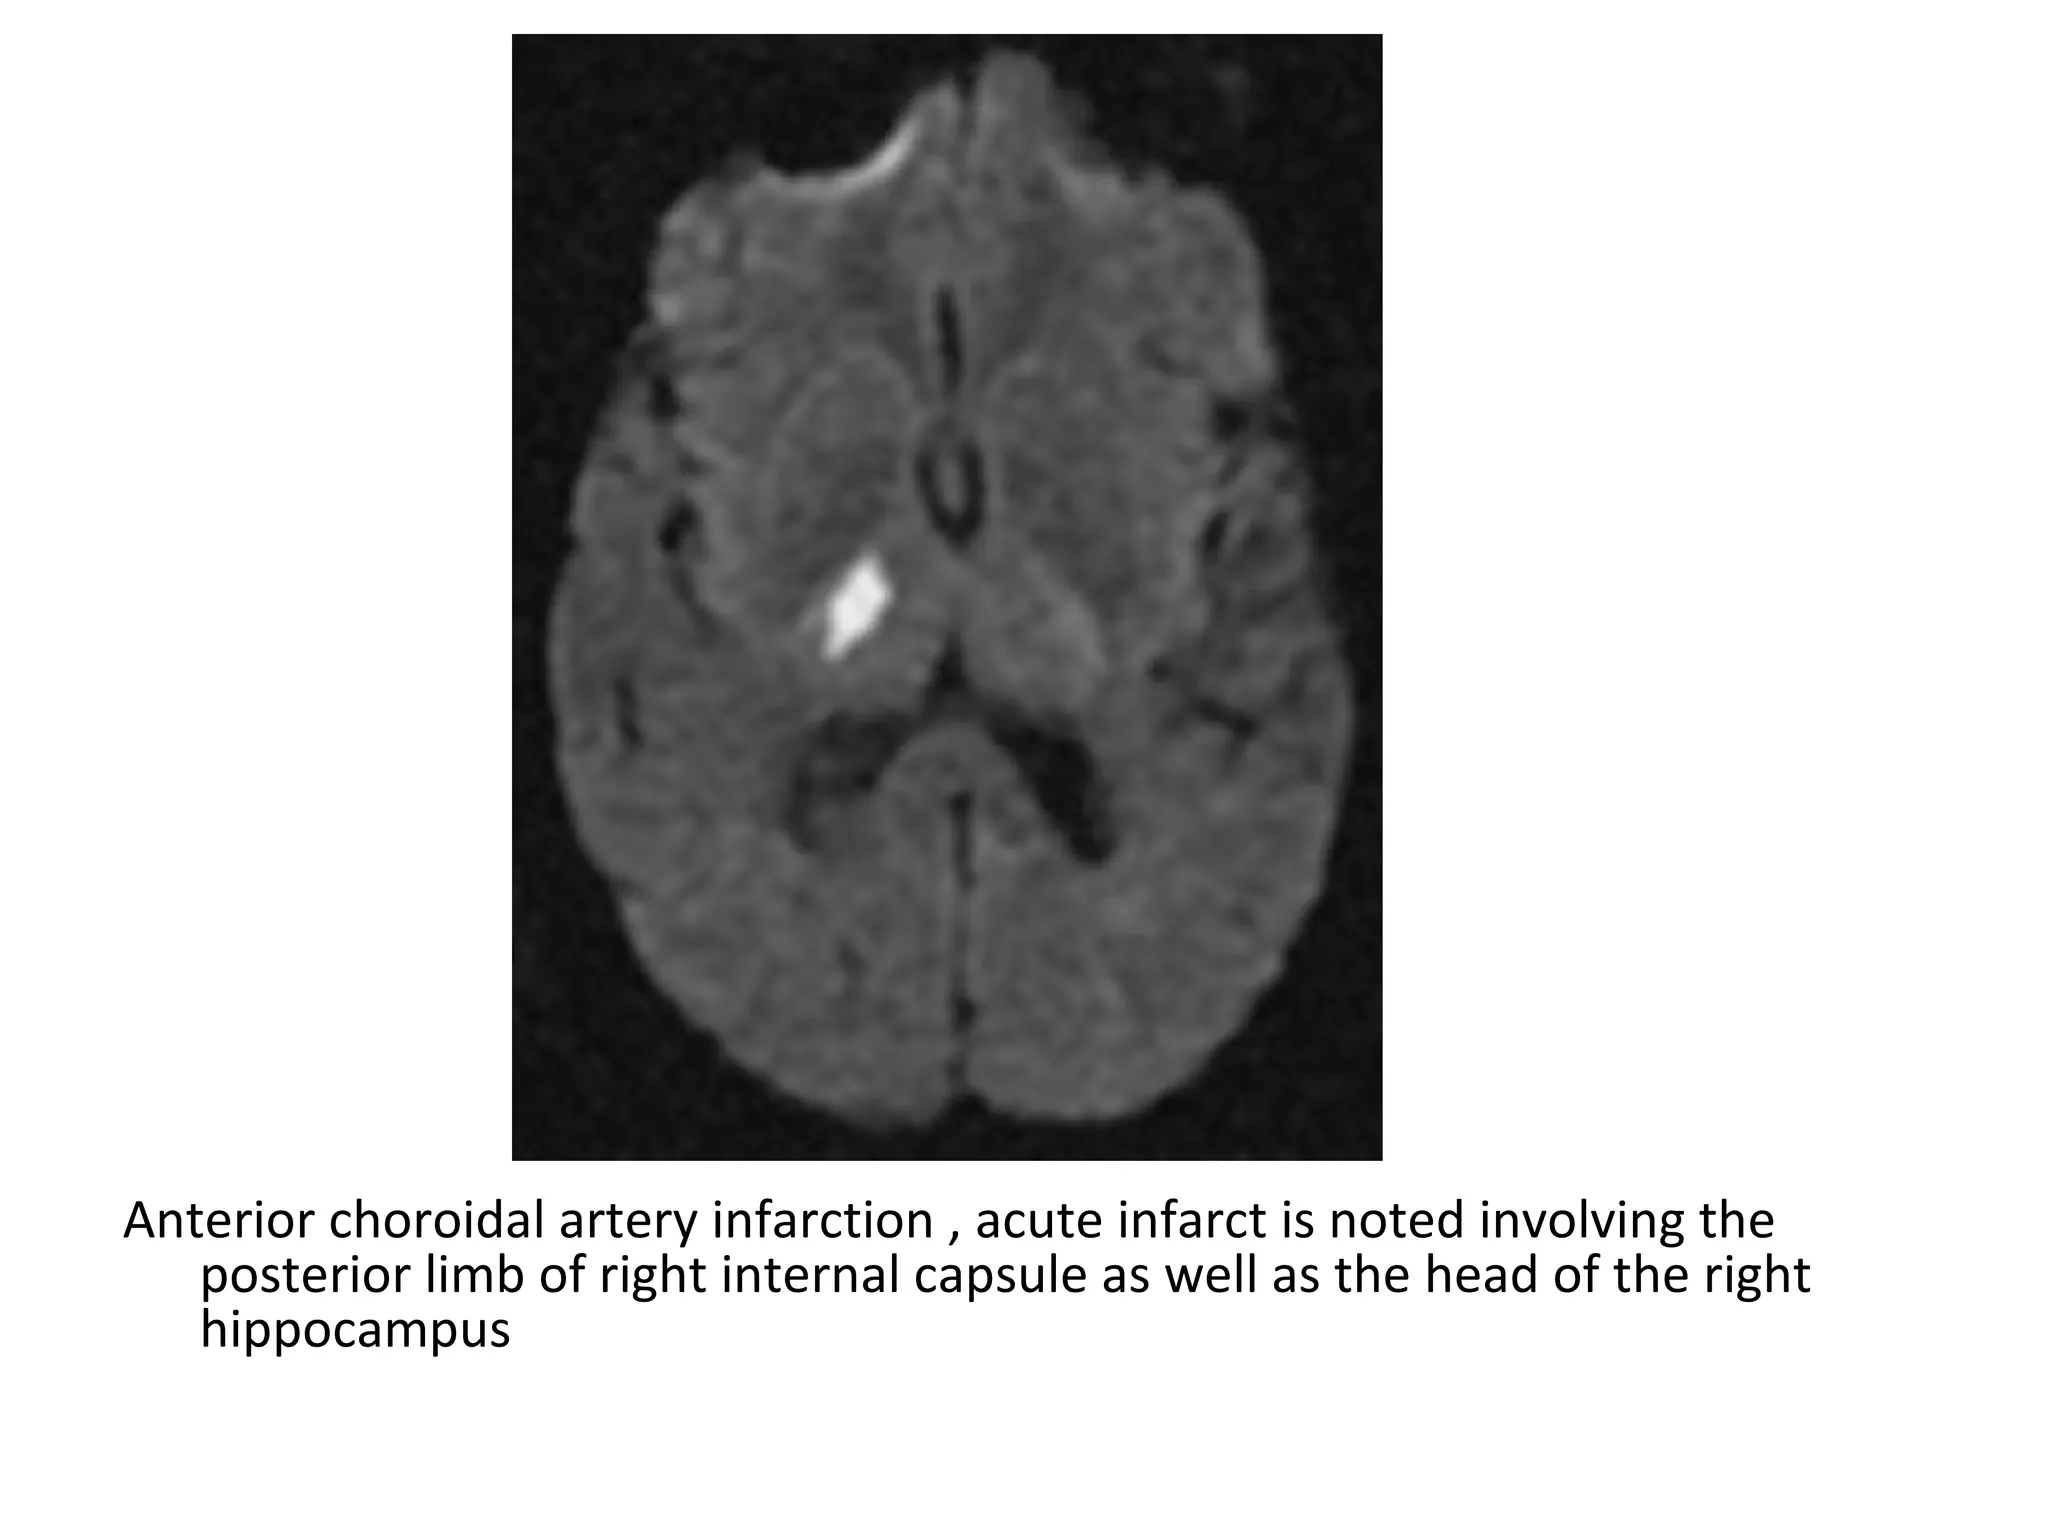

-The anterior choroidal artery is the most distal

branch of the ICA , it supplies the optic chiasm

, hippocampus and posterior limb of the

internal capsule

Anterior choroidal artery infarction , acute infarct is noted involving the

posterior limb of right internal capsule as well as the head of the right

hippocampus